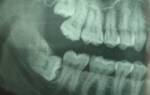

Сложное удаление зуба мудрости

Удаление зуба мудрости в данном случае, будет операцией сложной. Зуб мудрости расположен под значительным слоем кости, и находится в процессе формирования, однако уже представляет опасность для соседнего седьмого зуба, на котором на момент снимка есть признаки кариозного поражения в области щечного (на снимке, верхнего) бугра восьмерки. Наложение швов в данном случае обязательно. Послеоперационный период, будет сопровождаться пятидневным курсом антибиотикотерапии.